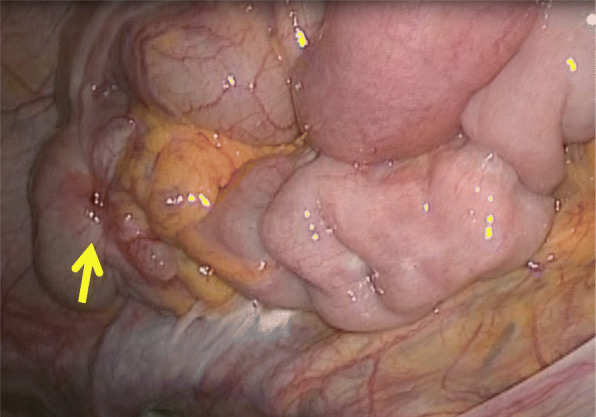

Laparoscopic surgery was performed for a diagnosis of the cecal tumor. The appendix could not be confirmed, and twitching and hardening of the serosa were observed in the ileocecal region, for which laparoscopic ileocecal resection was performed following the procedure for malignant disease. Lymph nodes were dissected up to the origin of the ileocolic artery following D3 dissection. No obviously enlarged lymph node was evident during surgery (Fig. 3).

Fig. 3.

The appendix could not be confirmed, and twitching and hardening of the serosa (arrow) were observed in the ileocecal region